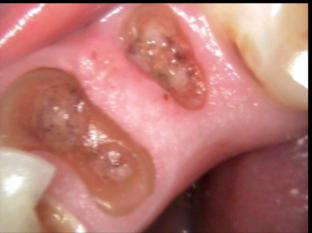

Intraoral Photograhs

Class IV